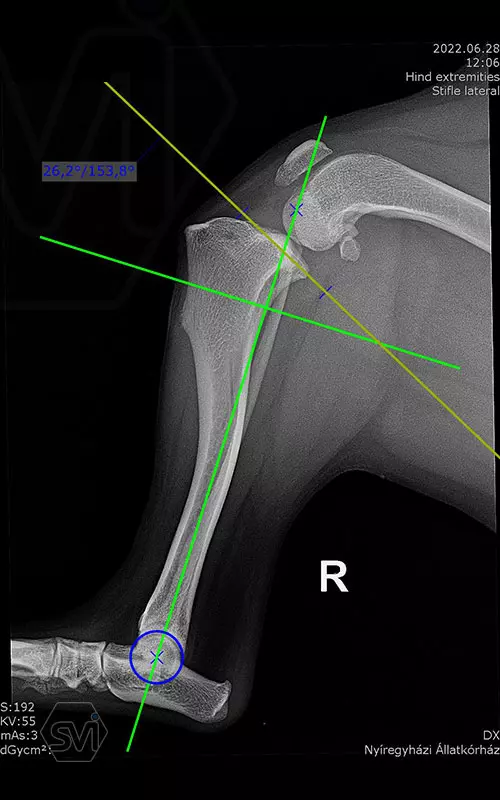

1,5 year old 13 kg mix dog underwent surgery today due to cranial cruciate ligament rupture and concomitant grade 3/4 medial patella luxation. During surgery, lateral tightening and medial loosening of the joint capsule (without opening the capsule) was performed. In the first phase of surgery, the 26-degree TPA was corrected simultaneously with the medial transposition of the proximal fragment. An R18 TPLO blade was used and the step and the rotation was fixed with a 2.7 precontured TPLO plate. The big curvature of the precontured plate provided an opportunity for placement without further conuring of the plate. The plate was temporarily fixed to the bone surface with two 1.2 K-nails using holes for temporary fixation. The distal piece was first stabilized with two locking screws. An AO 2,7mm srew was placed in the cranial hole of the proximal piece, which was able to create a significant tuberositas tibiae shift by tightening and simultaneously removing the temporaly, rotation stabilizing K-wire. Polyaxial locking screws are inserted into the remaining holes.

Thus, during surgery, we successfully applied a member of the precontured plate family designed for 2.7 mm screws for TPLO-M surgery.